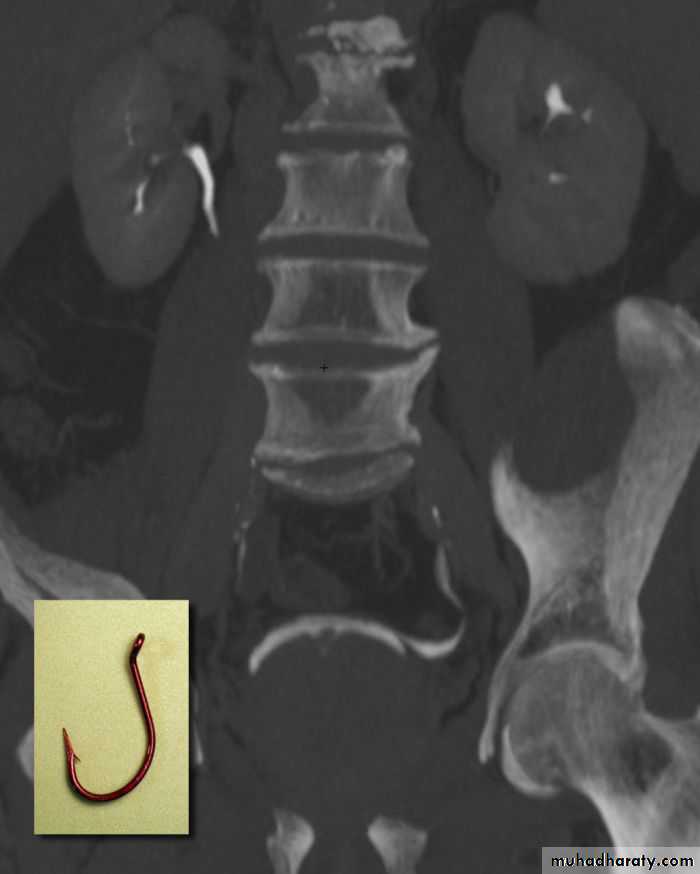

PROSTATIC Enlargement

Common cause of lower urinary obstruction . Either Benign prostatic hyperplasia or Carcinoma .Benign Hyperplasia :-

• IVU ( cystogram stage )

• * Elevated bladder base .• *Lower ureter elevated and curved (fish hook ).

• * Back pressure to both kidney & ureters .

• * Thick trabeculated bladder wall and diverticula formation .

• * Large size prostate produce filling defect like appearance .

• * Post-voiding residual volume .